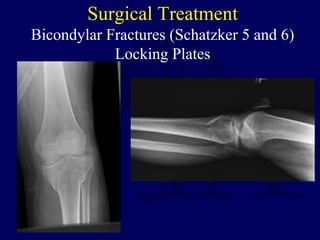

Surgical Treatment

Bicondylar Fractures (Schatzker 5 and 6)

Locking Plates